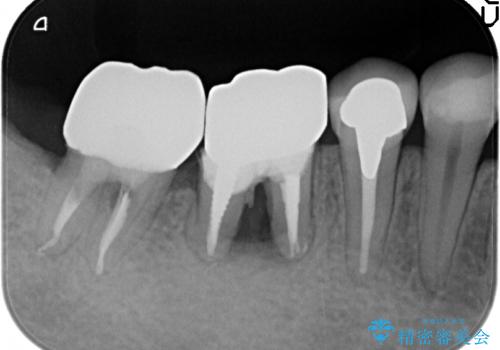

X線写真検査より、クラウンや銀歯の下で歯に大きな虫歯が発生し、抜歯を余儀なくされる状況でした。

虫歯に伴い歯槽骨の吸収も見られたので造骨後、インプラントを用いて咬合機能を回復します。